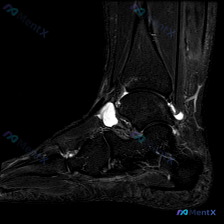

刚看到这份踝关节MRI的读片资料,整理一下病例和完整分析思路,这个病例的鉴别点其实挺典型的,分享给大家。 基本影像信息 这是一张踝关节MRI冠状位T2加权图像,针对影像的观察结果整理如下: 1. 骨性结构:胫骨、腓骨远端及距骨形态基本正常,骨髓信号无明显异常,没有急性骨挫伤、骨髓水肿,也没有明显游离...